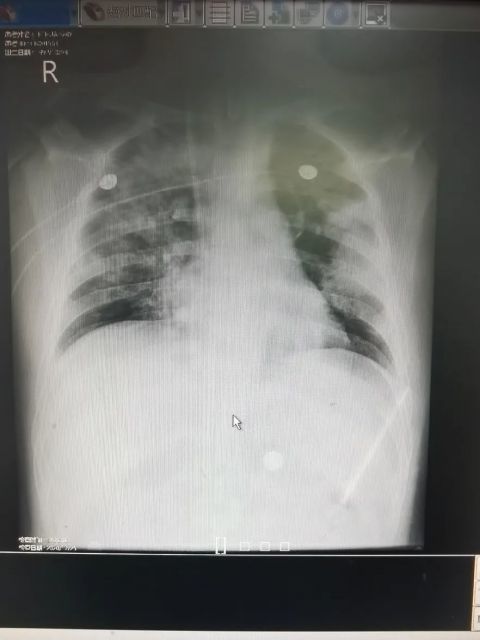

文章插图

治疗前胸片:双肺多发渗出灶 。